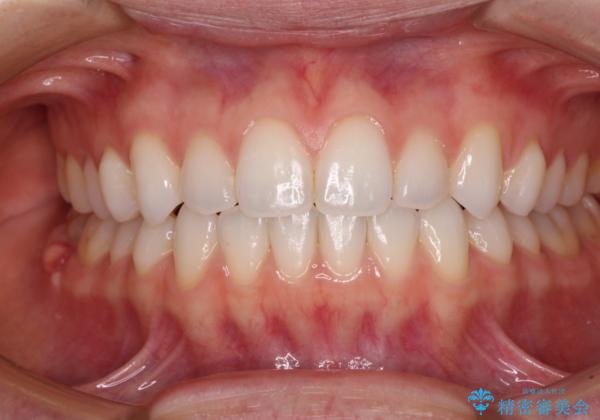

上下前歯が接触しない オープンバイトをインビザラインで改善

- 前歯の上下スペースによる食べにくさを気にして来院された患者様です。

インビザラインにより上下の前歯の隙間を閉じていくこととしました。

上下の奥歯を圧下させるようにすることで、前歯を接触させるように計画しました。

上下の隙間に舌が入り込むことがオープンバイトの原因であったため、舌の筋肉のトレーニングも並行して行い、後戻りの抑制を図りました。